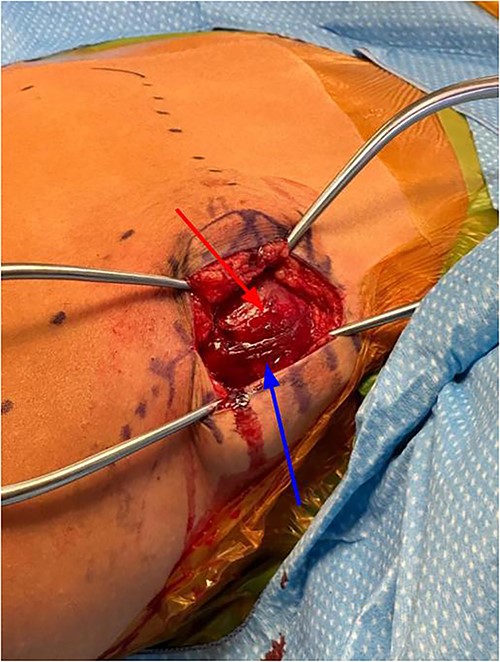

Subcutaneous tissue was divided with the electrocautery. Investing fascia over the trapezius was identified and the division between the superior and middle fibers of the trap was identified. The raphe between the superior and middle fibers was then bluntly spread in line (Fig. 3). We then encountered the superior aspect of the ventral lesion on the scapula (Fig. 4). Of note, the majority of levator scapulae fibers were medial to this lesion; however, the most lateral portion of the muscle was overlying the lesion. These lateral fibers were spread in line to expose the pedunculated mass. Blunt dissection was then taken circumferentially around the stalk of the mass to ensure all soft tissue had been freed from the area (Fig. 5). An osteotome was then carefully placed within the wound at the base of the stalk, and the tumor was then removed and sent to pathology for analysis. The stalk remnant was then filed down to a smooth and stable base with a rasp without any significant areas of potential irritation or prominence. The wound was then copiously irrigated with normal saline. Fluoroscopy images demonstrated complete resection of the bony tumor. There was no active bleeding within the wound. The fascia overlying the trapezius muscle and the skin were then closed.

Exposure after trapezius had been split between middle and superior fibers, levator scapula fibers can be seen medial to lesion (identified by arrow).